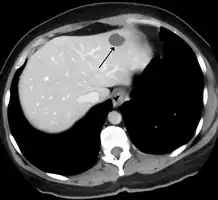

A liver hemangioma as seen on CT

Superficial IHs are situated higher in the skin and have a bright red, erythematous to reddish-purple appearance. Superficial lesions can be flat and telangiectatic, composed of a macule or patch of small, varied branching, capillary blood vessels. They can also be raised and elevated from the skin, forming papules and confluent bright-red plaques like raised islands. Infantile hemangiomas have historically been referred to “strawberry hemangiomas” in the past, as raised superficial hemangiomas can look like the side of a strawberry without seeds. Superficial IHs in certain locations, such as the posterior scalp, neck folds, and groin/perianal areas, are at potential risk of ulceration. Ulcerated hemangiomas can present as black crusted papules or plaques, or painful erosions or ulcers. Ulcerations are prone to secondary bacterial infections, which can present with yellow crusting, drainage, pain, or odor. Ulcerations are also at risk for bleeding, particularly deep lesions or in areas of friction. Multiple superficial hemangiomas, more than five, can be associated with extracutaneous hemangiomas, the most common being a liver (hepatic) hemangioma, and these infants warrant ultrasound examination.[6]

Large segmental hemangiomas of the head and neck can be associated with a disorder called PHACES syndrome.[12][13] Large segmental hemangiomas over the lumbar spine can be associated with dysraphism, renal, and urogenital problems in association with a disorder called LUMBAR syndrome. Multiple cutaneous hemangiomas in infants may be an indicator for liver hemangiomas. Screening for liver involvement is often recommended in infants with five or more skin hemangiomas.[14]